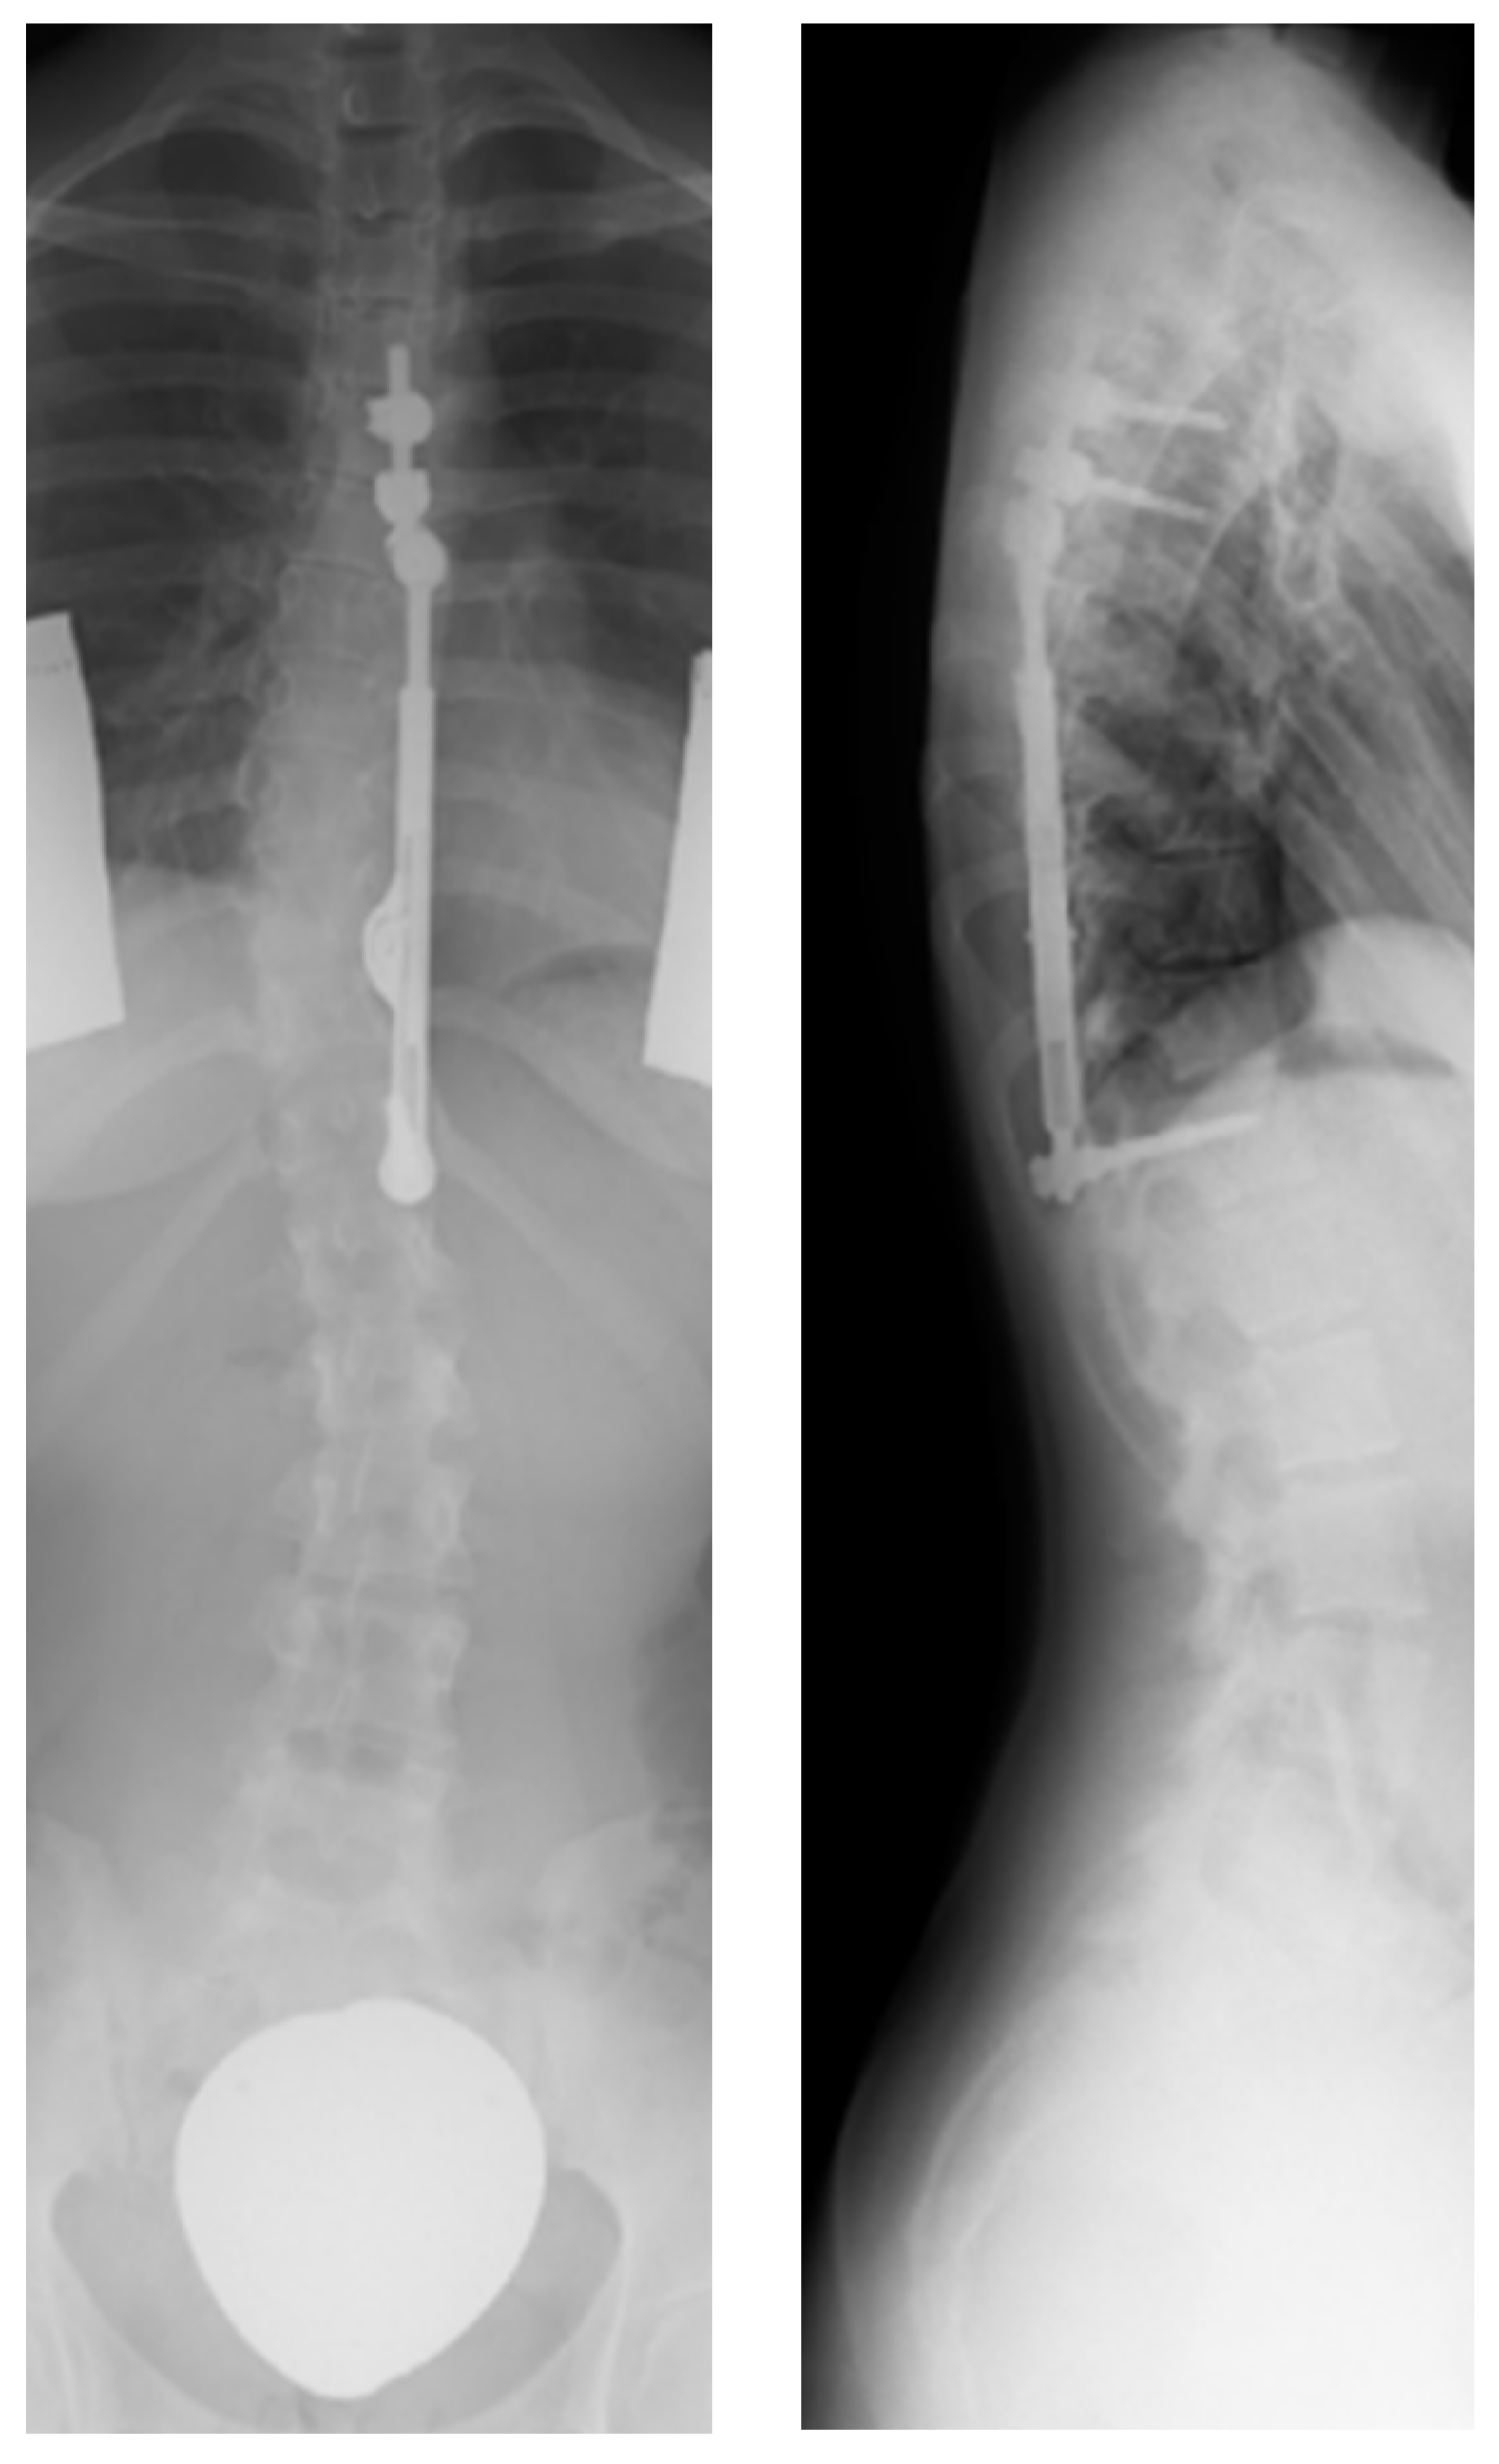

- Trobisch, P.D.; Kobbe, P.; Baroncini, A. Dynamic Scoliosis Correction as Alternative Treatment for Patients with Adolescent Idiopathic Scoliosis: A Non-Fusion Surgical Technique. Z. Orthop. Unfall. 2020, 158, 641–646. [Google Scholar] [CrossRef]

- Floman, Y.; Burnei, G.; Gavriliu, S.; Anekstein, Y.; Straticiuc, S.; Tunyogi-Csapo, M.; Mirovsky, Y.; Zarzycki, D.; Potaczek, T.; Arnin, U. Surgical management of moderate adolescent idiopathic scoliosis with ApiFix®: A short peri- apical fixation followed by post-operative curve reduction with exercises. Scoliosis 2015, 10, 4. [Google Scholar] [CrossRef] [PubMed]

- Floman, Y.; El-Hawary, R.; Lonner, B.S.; Betz, R.R.; Arnin, U. Vertebral growth modulation by posterior dynamic deformity correction device in skeletally immature patients with moderate adolescent idiopathic scoliosis. Spine Deform. 2021, 9, 149–153. [Google Scholar] [CrossRef] [PubMed]